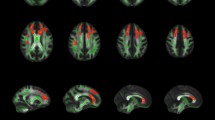

Our between-group analysis revealed significantly increased GM volume for the L2 group in several cerebellar areas bilaterally; the significant clusters appear in Table 1 and also in Fig. 1, overlaid on a standard brain template for illustrative purposes. No other significant differences were revealed. This finding suggests that learning and using an L2 can affect the structure of the cerebellum.

Since the cerebellum is part of the procedural memory network, it is, therefore, possible that increased cerebellar GM volume reflects efficient linguistic rule application by L2 learners. To investigate that, we calculated the GM volume of the cerebellar cluster that emerged from the VBM analysis; subsequently, we performed Pearson’s correlations between the participants’ cerebellar GM volume and their reaction times (RTs) in the behavioural task (apart from two participants who were excluded due to very low accuracy in the task). Only the RTs for trials that were accurately responded to were included in the analysis, and the two groups did not differ significantly in terms of accuracy (overall accuracy: L2, 94.5 % (5 %); NS, 97 % (3 %); F(1, 36) = 2.422, p = 0.128, η 2 = 0.063). For the L2 learners, the analysis revealed a significant negative correlation between the GM volume and their RTs in the regular morphology condition (r = −0.602, p = 0.014). This signifies that, the larger the cerebellar GM volume is, the more efficient the rule application in L2 becomes, expressed in shorter RTs. There were no significant correlations with the regular unrelated (r = −0.340, p = 0.197), irregular morphology (r = −0.042, p = 0.878) and irregular unrelated (r = −0.240, p = 0.371) conditions, indicating that a greater cerebellar GM is not generally beneficial for word reading or for performing lexical decisions. For the NS group, the analysis revealed no significant correlations with any of the four experimental conditions (regular morphology: r = 0.278, p = 0.222; regular unrelated: r = 0.293, p = 0.197; irregular morphology: r = 0.068, p = 0.769; irregular unrelated: r = −0.004, p = 0.987). Figure 2 shows the correlations per group for each of the four experimental conditions.